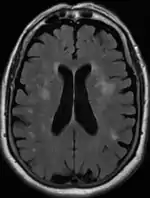

Leukoaraiosis is a particular abnormal change in appearance of white matter near the lateral ventricles. It is often seen in aged individuals, but sometimes in young adults.[1][2] On MRI, leukoaraiosis changes appear as white matter hyperintensities (WMHs) in T2 FLAIR images.[3][4] On CT scans, leukoaraiosis appears as hypodense periventricular white-matter lesions.[5]

The term "leukoaraiosis" was coined in 1986[6][7] by Hachinski, Potter, and Merskey as a descriptive term for rarefaction ("araiosis") of the white matter, showing up as decreased density on CT and increased signal intensity on T2/FLAIR sequences (white matter hyperintensities) performed as part of MRI brain scans.

These white matter changes are also commonly referred to as periventricular white matter disease, or white matter hyperintensities (WMH), due to their bright white appearance on T2 MRI scans. Many patients can have leukoaraiosis without any associated clinical abnormality. However, underlying vascular mechanisms are suspected to be the cause of the imaging findings. Hypertension, smoking, diabetes,[3] hyperhomocysteinemia, and heart diseases are all risk factors for leukoaraiosis.